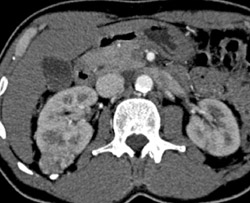

Diagnosis

Renal Cyst